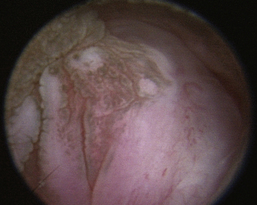

Normal turbinates have a smooth, pink-to-white surface and a spatial alignment that provides channels for the passage of air. The color varies and appears tan in the caudal nasal cavity. Turbinates come in different shapes and sizes, but the surface should be smooth. Ethmoid turbinates in the caudal nasal cavity will have a characteristic stippled or corrugated appearance (Figures 19-13 through 19-16). Ulcerations or various proliferations of the mucosa are indicative of disease. These changes are typically diffuse and accompanied by a lot of mucus. Mucus can be thin to purulent. Copious amounts can be flushed out of the nasal cavity to allow better visibility. The specific disease is determined by biopsy. After full examination of the nasal cavity, run the scope along the floor of the nasal sinus to the level of the choanae. Keeping the scope pointed in a ventral medial direction prevents inadvertent trauma or penetration of the cribriform plate. The index finger of the free hand can be used to follow the scope as it moves caudally over the hard palate; the surgeon can then palpate the scope through the soft palate when it moves into the nasopharynx. Some force is needed to complete this procedure and may result in increased bleeding.

Figure 19-15 Normal canine nasal turbinate mucosa.

image